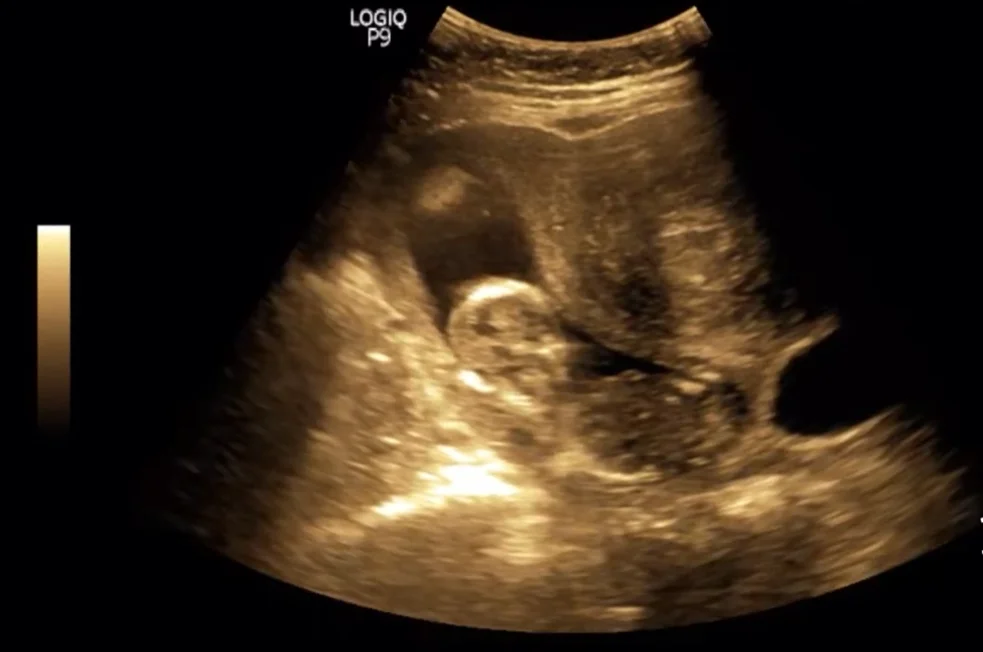

• U xơ tử cung trong thai kỳ (Myoma in Pregnancy)